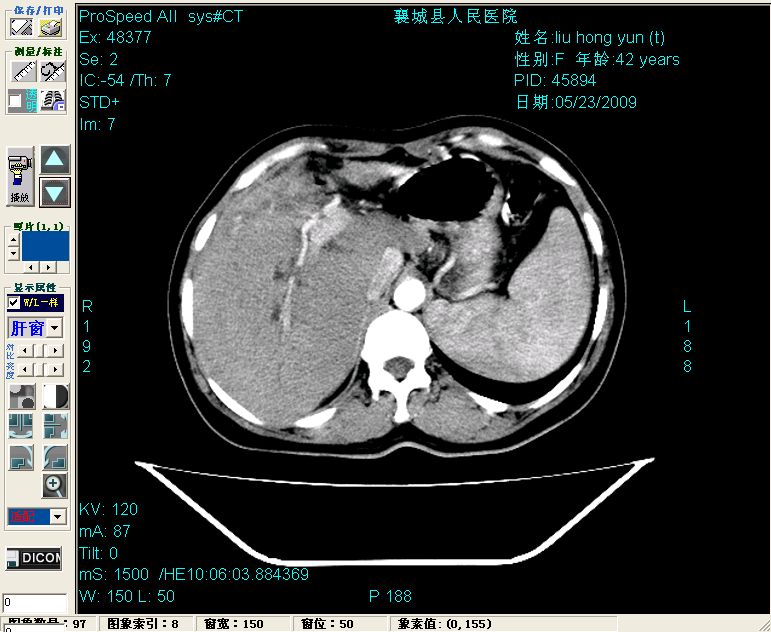

增强:

增强动脉期前述低密度区轻度早其强化,门脉期强化程度显著增高,延期扫描强化程度下降,但仍为相对高密度影

2左肝及右肝前叶表现考虑胆囊摘除术后所致的肝动门脉瘘形成,慢性纤维组织炎性增生.不完全除外左肝胆管细胞癌

1)肝内胆管结石,胆总管末端结石伴肝内胆管扩张。2)肝左叶及肝右叶前段增强前后之异常表现,考虑炎性改变,不排除胆管细胞癌。